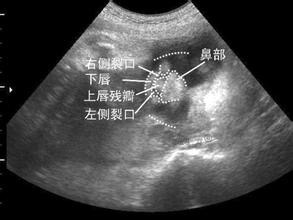

小李说:“今天检查后,医生说我的宝宝是唇裂,很明显!让我回家,谈谈该怎么办。虽然如今医疗条件很好,可以通过手术修复,但不能保证手术后看不出来!我该怎么办?”